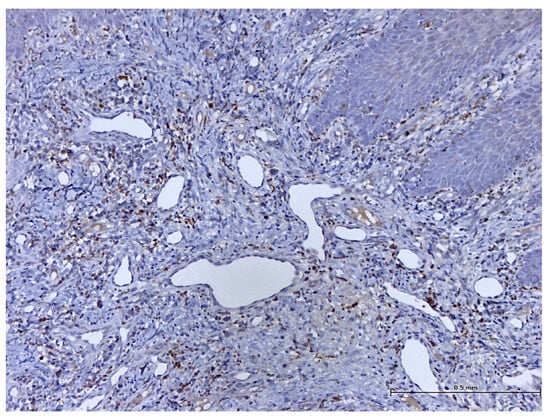

A Retrospective Histological Study on Palatal and Gingival Mucosa Changes during a Rapid Palatal Expansion Procedure

3. Results